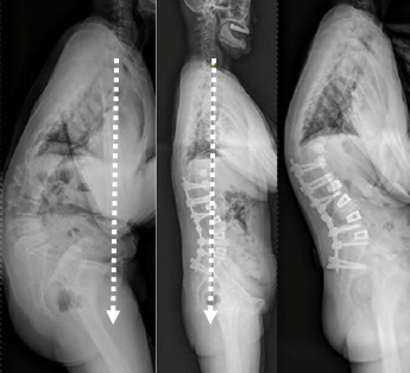

图7 术前-术后1个月-术后1个月外观

1) 矢状面失平衡(High SVA)过度矫正

术前-术后SVA矫正过大(大于5cm)的患者,PJK发生的风险增高

矫形术后矢状面失平衡可增加固定融合近端和远端交界区的应力,增加PJK风险

图16 矢状面失平衡过度矫正

2)腰椎前凸(LL)过度矫正

图17 据文献报道,腰椎前凸(LL)过度矫正和SVA基线位置不当,均为增加PJK发生的风险因素